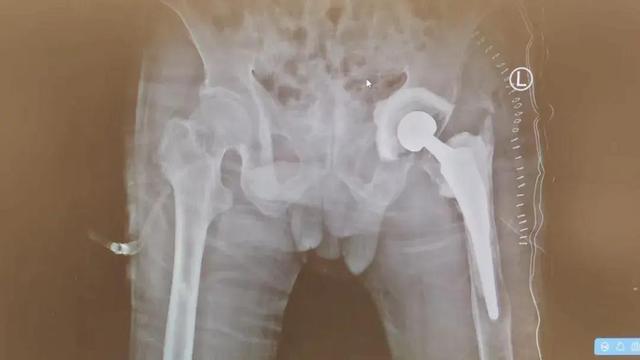

术后影像

在医护人员的严密监护与精心治疗下,陈依伯很快从ICU转出,并在康复师的个性化康复指导下,身体机能一天天恢复并顺利出院。